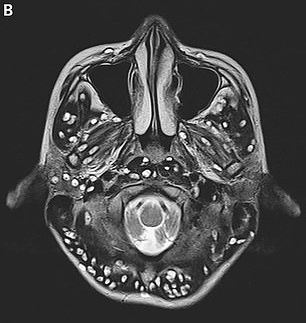

An MRI that was conducted on his brain to check the reason of his death showed cysts throughout his brain. It was spread like a wildfire in his brain. The cysts had converted into a life-threatening condition called neurocysticercosis which killed the young man.

Faridabad’s ESIC Medical College’s doctor Nishanth Dev submitted the case to The New England Journal of Medicine. He was the one who treated the patient who lost his life to neurocysticercosis.